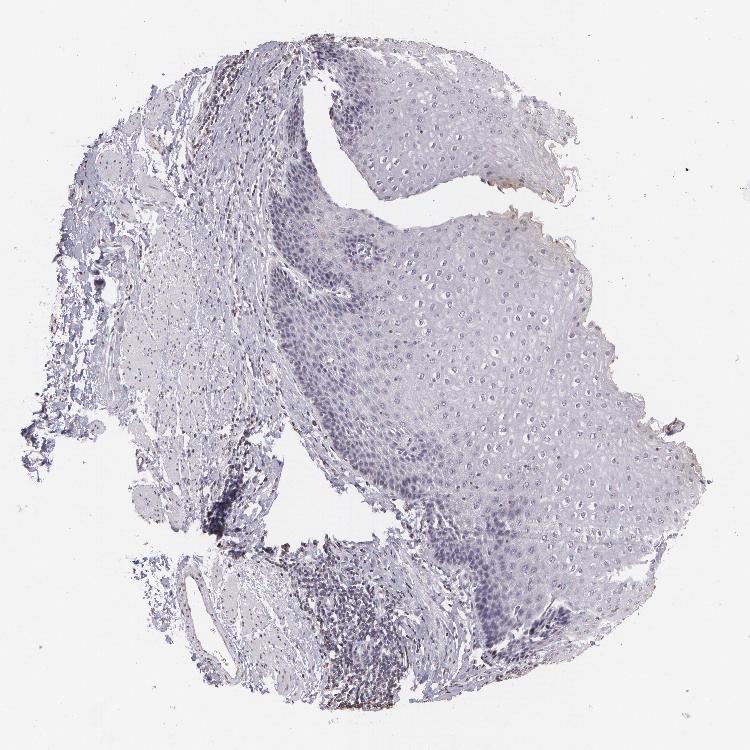

ESOPHAGUS - Antibody stainingi

Antibody staining in the annotated cell types in the current human tissue is reported as not detected, low, medium, or high, based on conventional immunohistochemistry profiling in selected tissues. This score is based on the combination of the staining intensity and fraction of stained cells.

Each image is clickable and will lead to virtual microscopy that enables deeper exploration of all samples and also displays staining intensity scores, fraction scores and subcellular localization as well as patient and tissue information for each sample.

Antibody HPA004179Antibody HPA007235Antibody HPA008855Antibody CAB000036Antibody CAB001986Antibody CAB080102Antibody CAB080103

Squamous epithelial cells HighLowLowMediumNot detectedNot detectedNot detected